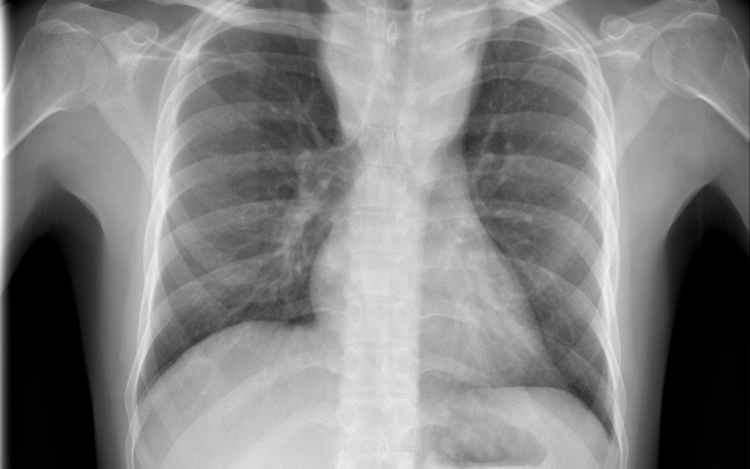

Csökkent a tbc-fertőzések száma Európában

Átlagosan 4,3 százalékkal csökkent az új tuberkulózisos (tbc-s) esetek száma 2010 és 2014 között az Egészségügyi Világszervezet (WHO) 53 országot magába foglaló európai régiójában.

A becslések szerint 2014-ben 340 ezer európai betegedett meg tuberkulózisban, ami százezer emberre vetítve 37 esetnek felel meg. Azzal, hogy 2010 és 2014 között átlagosan 4,3 százalékkal csökkent az új esetek száma, az európai régió teljesítette azt a millenniumi fejlesztési célt, hogy 2015-re visszafordítja a tbc terjedésének tendenciáját.

Magyarországon biztonságos a tbc-re vonatkozó epidemiológiai helyzet: 2014-ben nyolc új eset jutott százezer lakosra, és az előzetes adatok szerint ugyanez igaz a 2015-ös évre is. Így a WHO Magyarországot az alacsonyan átfertőzött országok között tartja nyilván. Alacsony a multirezisztens esetek száma - 2014-ben hét új esetet észleltek -, valamint a gyermekkori megbetegedéseké is: 2014-ben hat 14 éven aluli gyermek betegedett meg.

A WHO a legnagyobb kockázatnak kitett csoportok célzott tbc-szűrését javasolja, Magyarországon 2014 óta eszerint szervezik meg a kötelező tüdőszűrést.